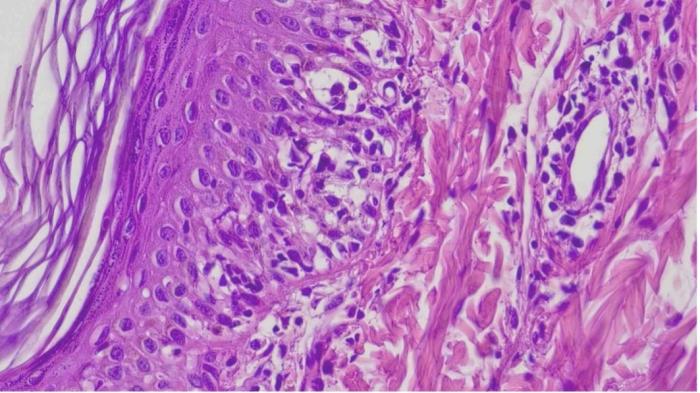

Tras 10 días de tratamiento, las lesiones mostraron una mejoría leve, por lo que se decidió obtener múltiples muestras mediante biopsia cutánea con trocar de 6 mm. El examen histopatológico evidenció un patrón inflamatorio compuesto principalmente por linfocitos que afectaba la unión dermoepidérmica, con vacuolización ocasional y apoptosis de queratinocitos, especialmente a nivel basal, compatible con una dermatitis de la unión citotóxica (Figura 4 y 5).

Los hallazgos histopatológicos típicos de esta patología consisten en una dermatitis de interfase linfocítica rica en células, caracterizada por un infiltrado dérmico prominente en banda (patrón liquenoide), compuesto principalmente por linfocitos y células plasmáticas, y acompañado de incontinencia pigmentaria (ver Figura 4 y 5).